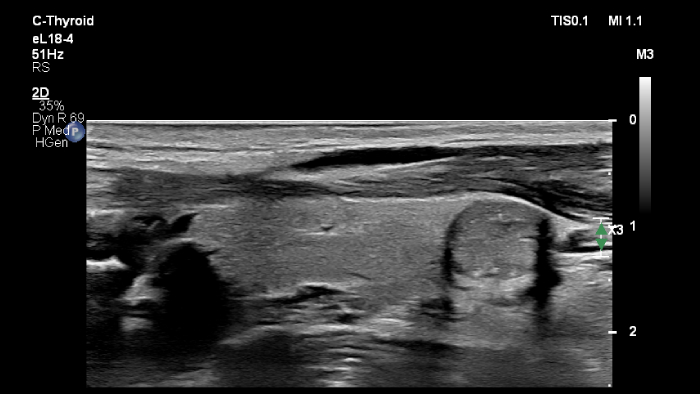

O transdutor PureWave eL18-4 da Philips inclui matrizes de cristais multilinhas que proporcionam imagens de corte fino para uma excecional resolução dos detalhes, ao mesmo tempo que fornece imagens e penetração extraordinárias.

O MicroFlow Imaging ultrapassa muitas das barreiras associadas aos métodos convencionais para a deteção do fluxo sanguíneo de vasos pequenos com alta resolução e artefactos mínimos.